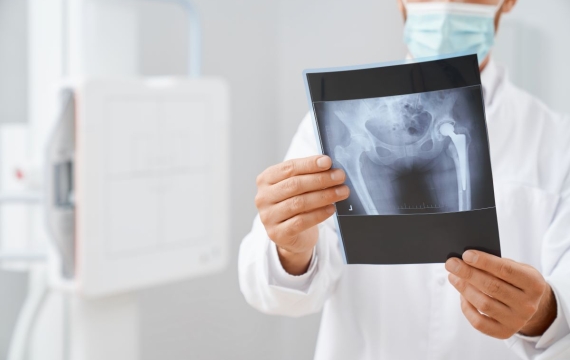

Una radiografía es una prueba radiológica que permite obtener imágenes de los huesos, órganos y tejidos del cuerpo, mediante el uso de rayos X. Las partes más densas aparecen en los resultados en diferentes tonos en una escala de grises.

Se utiliza comúnmente para diagnosticar huesos fracturados o dislocación de articulaciones. Las radiografías de huesos son la forma más rápida y fácil para su médico de ver y evaluar fracturas de hueso, lesiones, y anormalidades en las articulaciones.